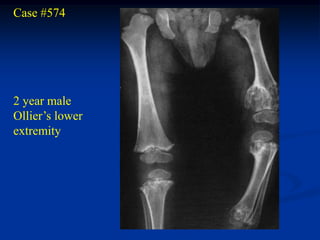

Case #574

2 year male

Ollier’s lower

extremity